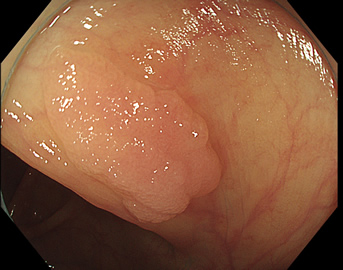

特に、下のような「Ub型(全く凸凹の無い完全に平坦な病変)」は、以前は「ほとんど見つからなかった」のが、TXIを使うようになってから「日常的に」見つかるようになりました。

通常観察 TXIモード

青い色素は追加していません![]()